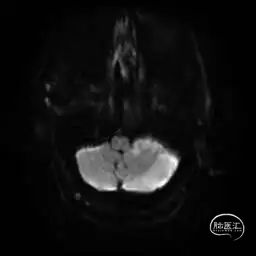

MRI提示小脑缺血性改变。

术后9天MRI: